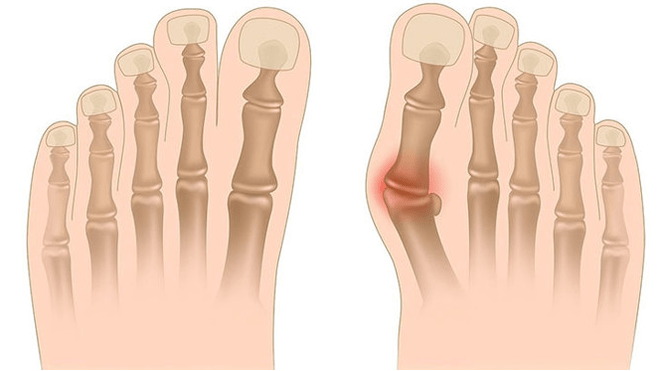

Valgus deformation is the curvature of the foot characterized by the equalization of its longitudinal arch.Usually the inner edge of the foot is descended ("drops") and the heel turns out.

When you take your legs (if you look at them from the back), a deformation similar to X is formed at the ankle level: the ankles are in contact while the heels are 5-6 centimeters apart.

In the third stage, the protruding of the thawed bone is determined (noticeably the lower ankle on the inner surface of the ankle), as well as a strong deviation of the heel outside (the patient is based on the inner edge of the heel bone).

The advanced deformation of Valgus of the feet is characterized by a pronounced curvature of both the leg itself and the ankle joint.Patients complain of burning pain in the lower leg muscles, as well as a significant impairment of the gait: the knees rub against each other until the right and left legs are located at some distance.